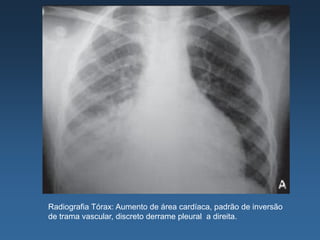

Radiografia Tórax: Aumento de área cardíaca, padrão de inversão

de trama vascular, discreto derrame pleural a direita.

• ECG: RS, FC: 106 spm, BDASE, ARV difusa, com ondas T

negativas em parede antero-lateral

• Eco TT: Hipocinesia difusa, FE: 30%; VEs: 54; VEd: 63; AE:

60; PSAP: 50 mmHg.Refluxos mitral discreto.

• Ressonância de Coração: FE: 23% (Simpson); -

Acinesia antero-septal e inferior. Hipocontratilidade dos

demais segmentos. Área de realce tardio em parede

ântero-septal basal, podendo ser compatível com lesão

por miocardite.